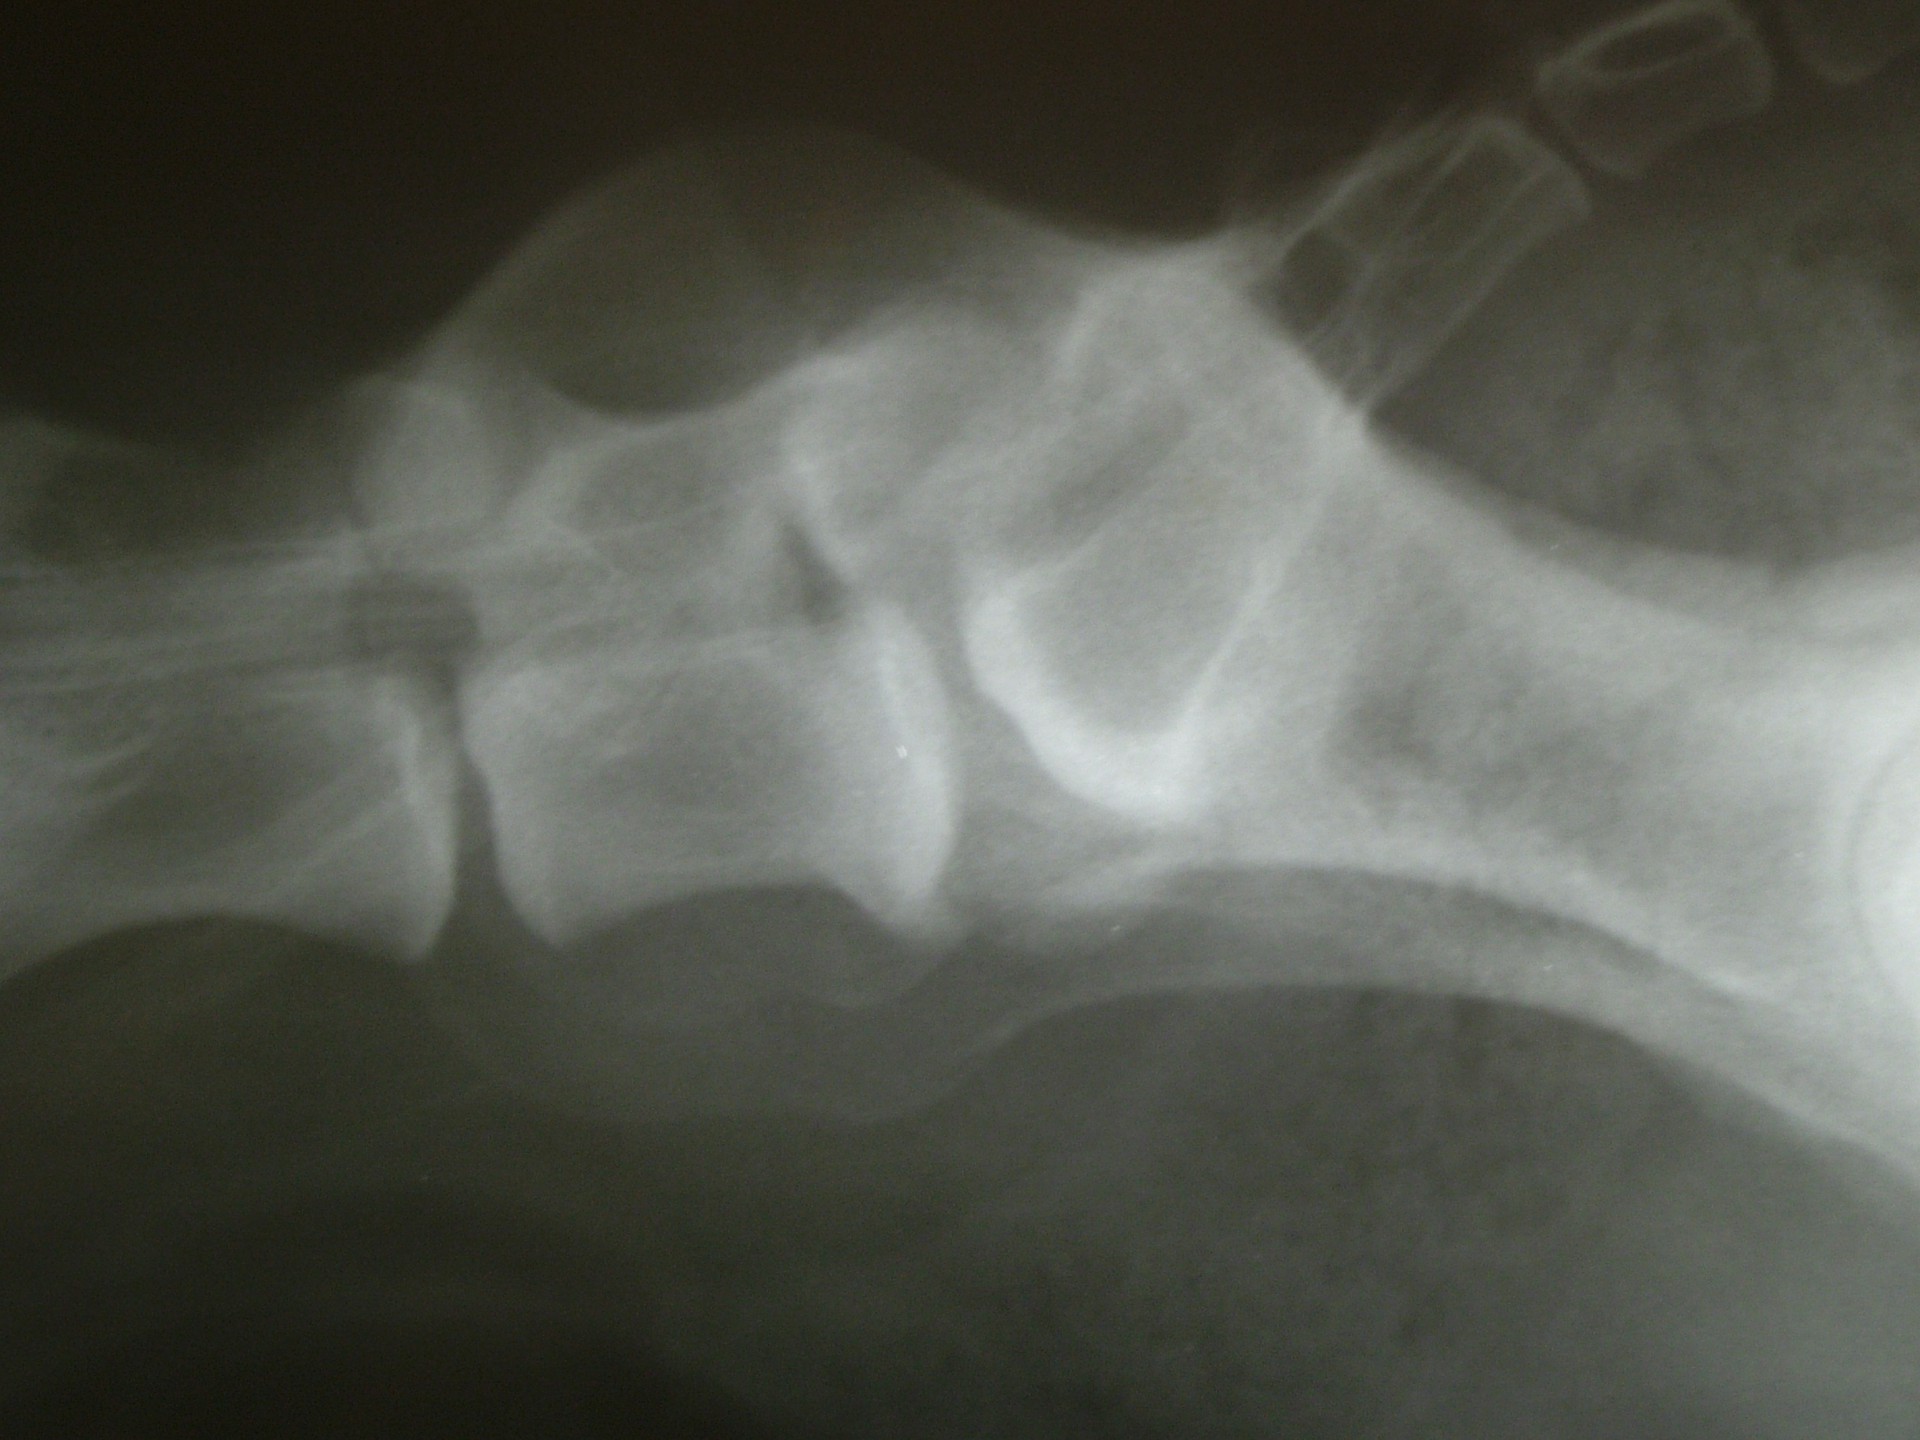

A C.E.C diagnosztikájának legfontosabb lépése a kórelőzmény megismerése után (hátulsó testfél gyengeség, rogyadozás, széklet-vizeletürítési problémák, fájdalom stb.) az alapos klinikai vizsgálat, mely során a gerinctájék fájdalmasságát, a hátulsó végtag reflexeit, a fájdalomérzet meglétét vizsgáljuk.Amennyiben a klinikai tünetek indokolják kiegészítő vizsgálatként elsősorban a röntgenvizsgálat jön szóba, mely során a gerincoszlop ezen szakaszáról oldalirányú felvételt készítünk.

Amennyiben a klinikai tünetek és az oldalirányú röntgenfelvétel alapján a C.E.C. alapos gyanúja felmerül további vizsgálatokkal kell kizárnunk egyéb gerincbetegségeket ill. megerősíteni a C.E.C. diagnózisát.

Az egyik ilyen vizsgálat a gerincfestés vagy myelographia, mely során a gerincvelőt körbevevő térbe (subduralis tér), az agy-gerincvelői folyadékba (liquor) röntgenkontraszt anyagot juttatunk és sorozatos felvételekkel ellenőrizzük annak áramlását. Ennek előnye, hogy a kontrasztanyag lefutása során az egyéb gerincszakaszok is kirajzolódnak, és ezek esetleges betegségeit is diagnosztizálhatjuk. A gerincoszlop hátsó szakaszáról 1db teljesen hajlított és 1 db teljesen nyújtott beállítású RTG felvételt készítünk. Ha a két felvétel között jelentős különbséget tapasztalunk a C.E.C. biztosan diagnosztizálható.A másik invazív diagnosztikai eljárás a durographia, mely során a röntgenkontraszt anyagot a durazsák körüli térbe (epiduralis tér) juttatjuk és így indirekt módon ábrázoljuk a gerincvelő esetleges összenyomatását. A vizsgálat során a kontrasztanyag telődési hiánya jelzi az összenyomatást és annak mértékét.A diagnosztika legmodernebb vizsgálati módszere az MRI vizsgálat, mely során altatásban, invazív beavatkozás nélkül kaphatunk átfogó képet a vizsgálni kívánt gerincszakaszról. Magyarországon állatorvosi diagnosztikai célra csak a Kaposvári Egyetem Diagnosztikai és Onkoradiológiai Intézetében működő berendezés használható.